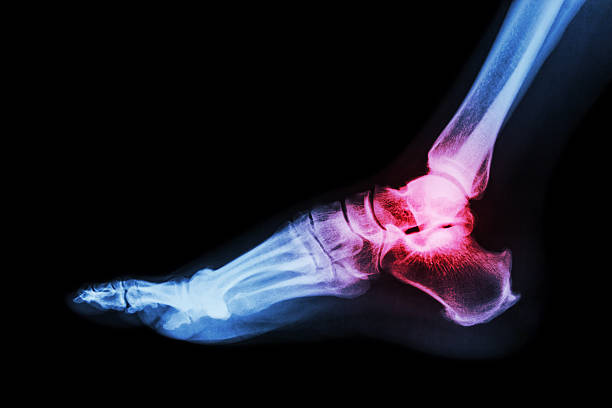

1. 내과 골절

발의 관절이 안쪽으로 강하게 뒤틀어지면 발목과 연결된 거골에 밀려 내과골절이 발생할 수 있고, 뼈가 어긋남 없이 골절되었다면 깁스 등의 보존적 치료등을 하게 됩니다. 하지만, 골절부위가 어긋난 버린 상태라면 스크루핀 등으로 고정하는 수술을 할 가능성이 있습니다.